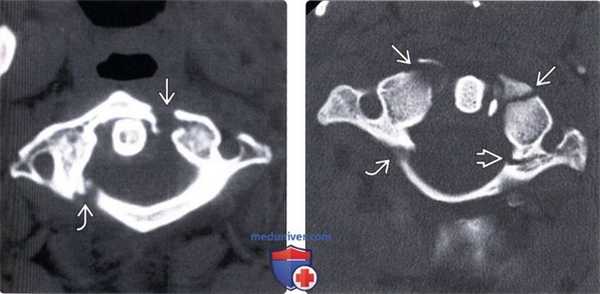

(Слева) КТ, аксиальный срез: взрывной перелом передней и задней дуг С1 с боковым расхождением фрагментов.

(Справа) КТ, аксиальный срез: симметричные переломы передней дуги С1, правой боковой части задней дуги и левой боковой массы, последняя линия перелома распространяется на отверстие поперечного отростка.